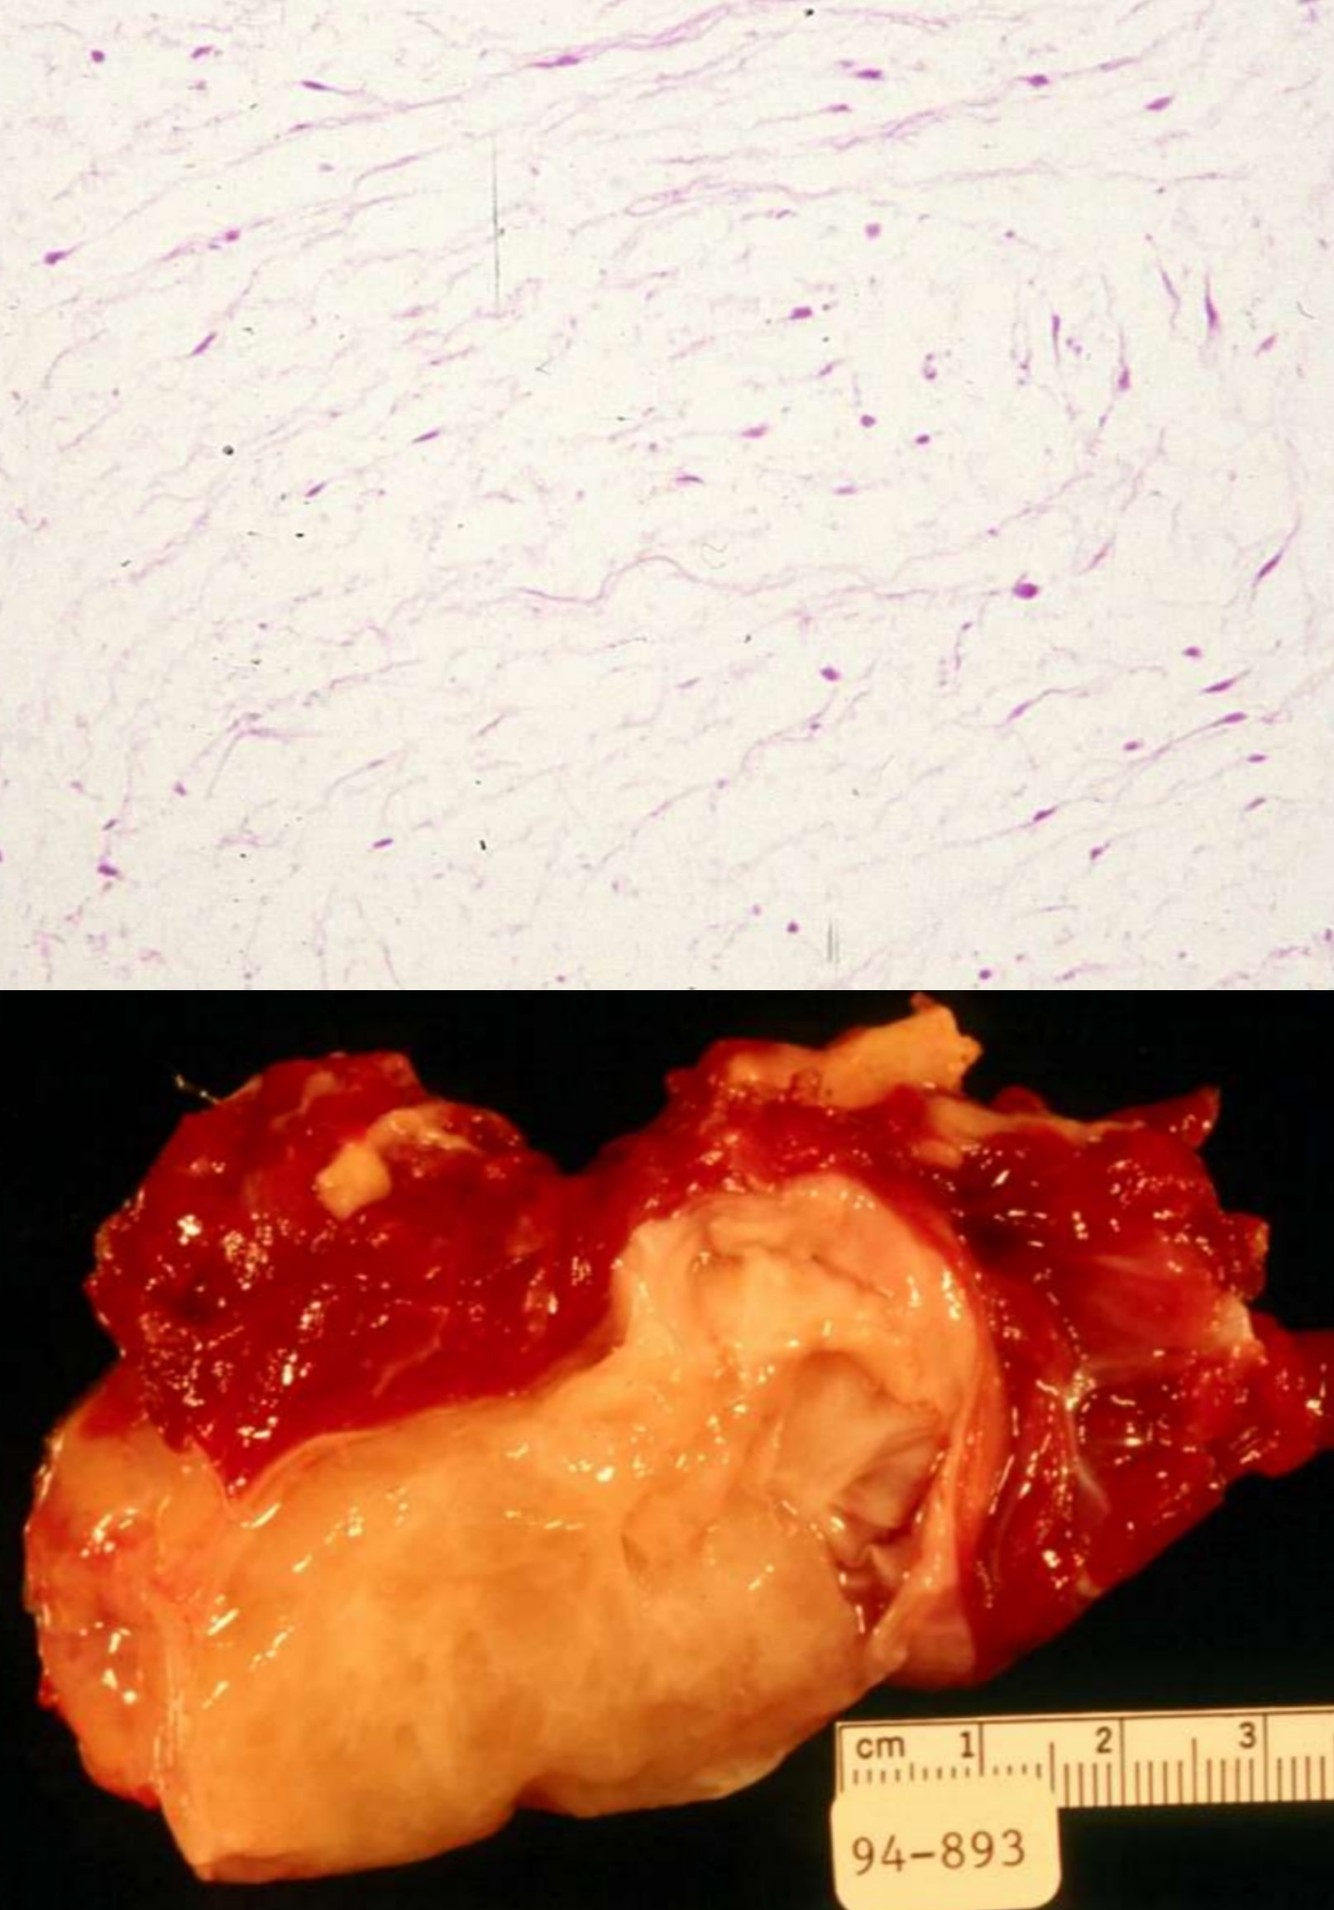

SPINDLE CELL LIPOMA

• Subcutaneous mass, posterior neck, shoulder and upper back

• Similar tumors elsewhere classified as atypical lipomatous tumors or well differentiated liposarcoma if deep

• Men 90%, 45-65 yo

• Genetics:

• 16q or 13q abnormalities in 70%

• Frequently hypodiploid

• Gross:

• Usually 3-5 cm, well circumscribed, yellow-gray-white, firmer than classic lipoma

• Histology:

• Mature adipose tissue, spindled cells, and ropy collagen

• Floret-like multinucleated giant cells –> pleomorphic lipoma

• CD 34+

ATYPICAL LIPOMATOUS TUMOR / WELL-DIFFERENTIATED LIPOSARCOMA

• One of the most common soft tissue sarcoma of adulthood

• lower extremities and retroperitoneum

• Ring or giant marker/rod chromosomes derived from 12q13-15 in almost all cases

• Amplifications of the 12q12-21 and 10p11-14 regions

• MDM2 and CDK4 by FISH or real time PCR can differentiate from other sarcomas

• Carboxypeptidase M amplification may be alternative diagnostic tool

• Other rearrangements include amplifications of 12q12-21 and 10p11-14 regions

• Histology

• Mature fat plus variably sized adipocytes and fibromyxoid stroma containing spindle cells with large, deep-staining nuclei and marked nuclear enlargement or pleomorphism

• Cellularity is low and mitotic figures are uncommon

• Usually fibrous tissue septa are present that may contain spindle cells or highly pleomorphic cells

• Some nuclei have sharply outlined vacuoles (Lochkern)

• Rarely heterologous differentiation

• No/few lipoblasts

• May be associated with metaplastic bone formation

• Rarely has low grade osteosarcomatous component

• Includes lipoma-like and sclerosing variants

• Stains:

• Postive: MDM2 and CDK4 (both together are sensitive and specific, S100 (adipocytes in 2/3 of cases), CD34 (some spindle cells), Usually p16

• Negative: HMB45